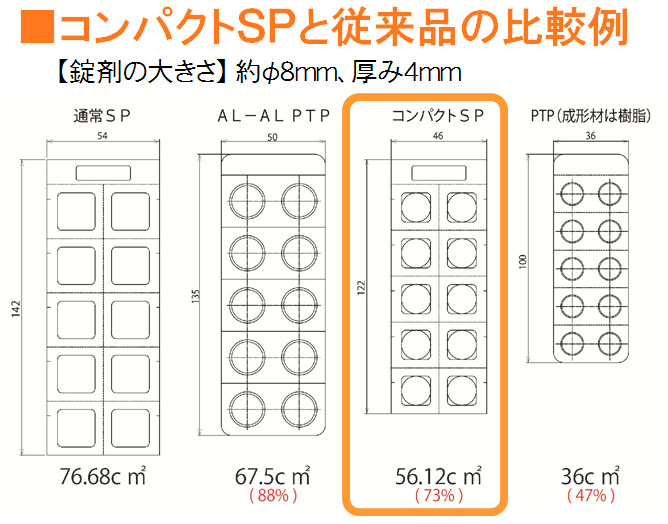

薬の誤飲対策 コンパクトな包装形態 コンパクトsp 株式会社カナエ

薬の誤飲対策 コンパクトな包装形態 コンパクトsp 株式会社カナエ